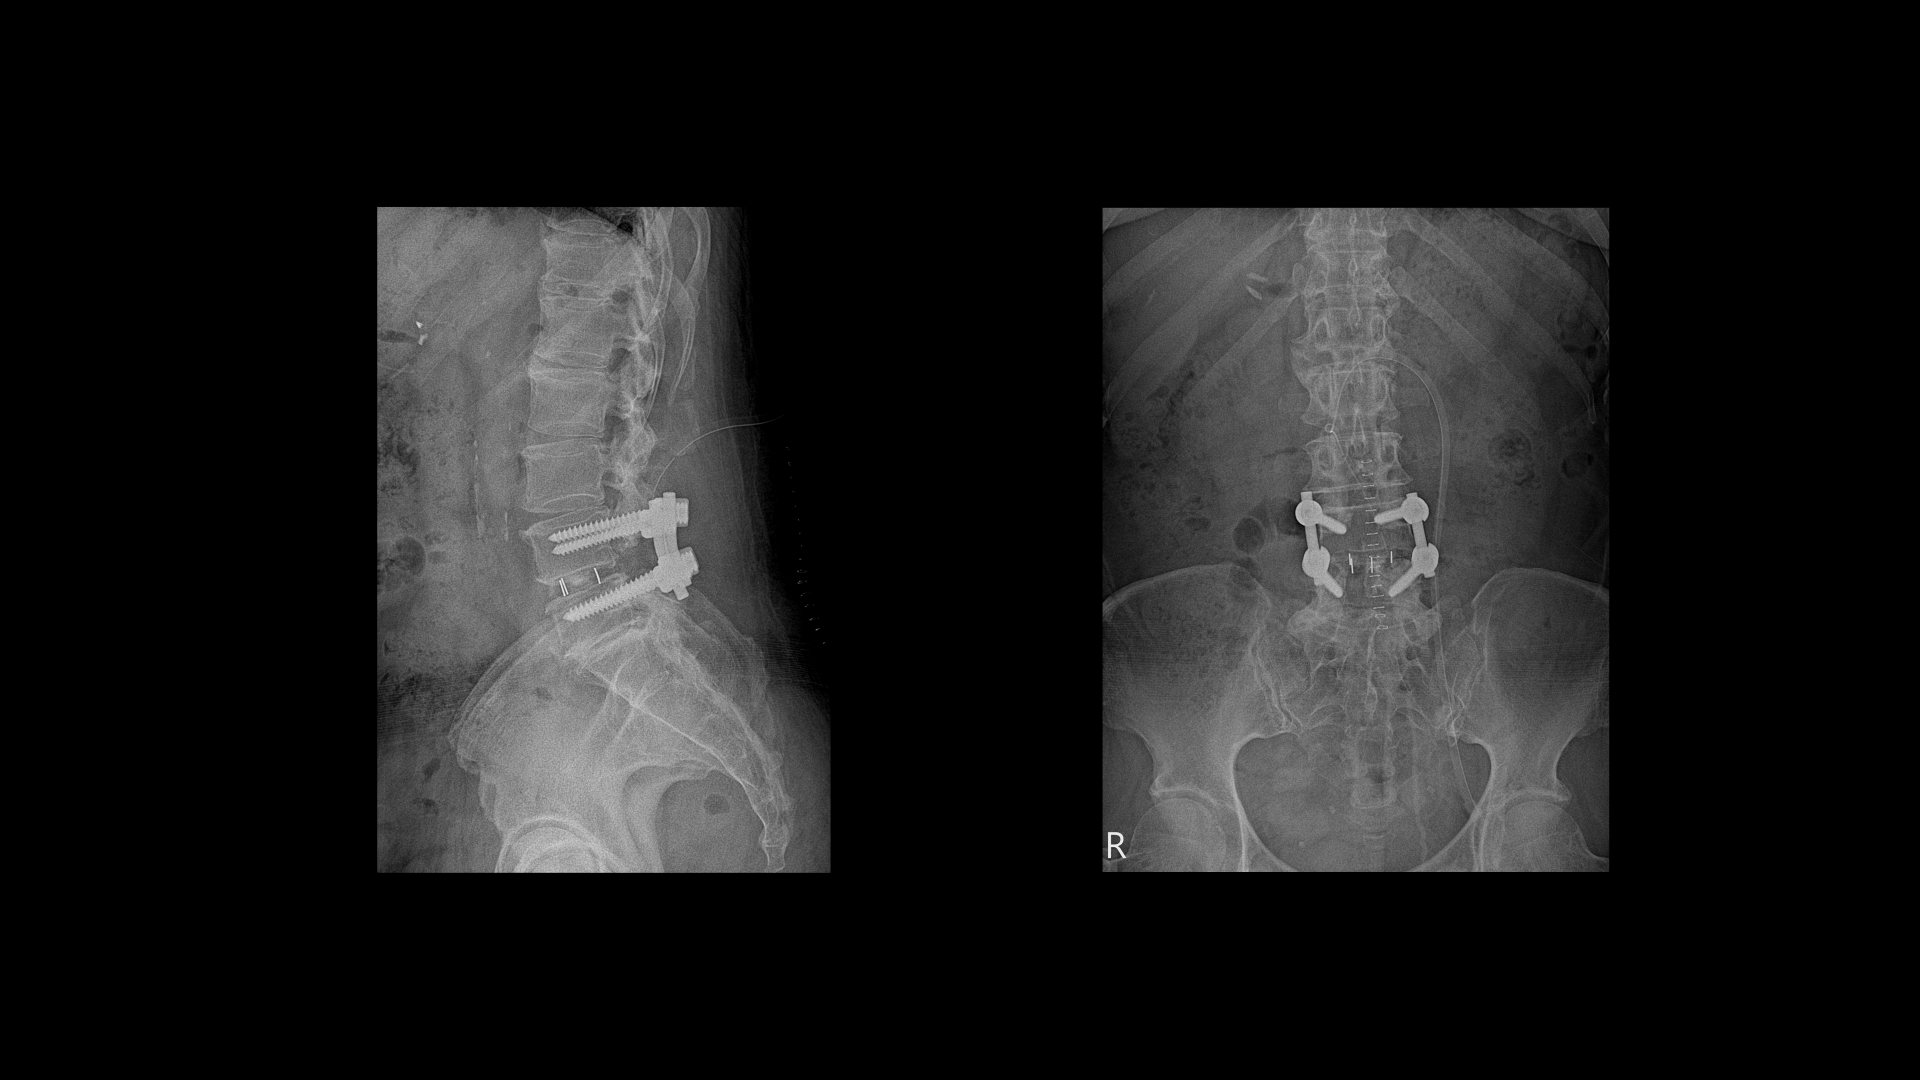

올해 초에 디스크가 4번 5번에서 또 오른쪽으로 심하게 터져서 결국은 후궁과 후관절, 황색인대를 모두 다 제거하고 나사를 박는 유합술을 하셨습니다.

오른쪽 다리가 갑자기 저려서 그냥 그대로 주저 앉아서 힘이 하나도 없어가지고 처음에는 시술을 했어요. 그리고 나서 한 6개월 만에 다시 디스크가 터져버려서 이번에는 수술을 했죠. 유합술 했어요. 척추 3번 4번이 협착됐다가 4번 5번이 터져버렸어요. 그래서 그건 유합술이 아니면 안 된다 해서 나사 박는 수술을 했거든요. 수술 전에는 방사통이 양쪽 다 왔는데 특히 오른쪽이 더 심했어요.

저는 다른 사람보다 더 크게 수술을 했었거든요. 수술 자리가 너무 부어 있으니 신경을 눌러서 그럴 것이다. 1년 이상을 기다려라 그랬어요. 저는 수술만 하면 완전히 좋아질 줄 알았죠. 저는 이 수술이 마지막이라고 생각하는데 솔직히 걱정스럽죠. 잘 돼야 하는데 만약에 잘못될까 싶은 생각들이 있어요. 이제 내 뼈만 아니라 다른 뼈가 들어가 있어서 만약에 잘못되면 어쩔까 마음이 심란해요.